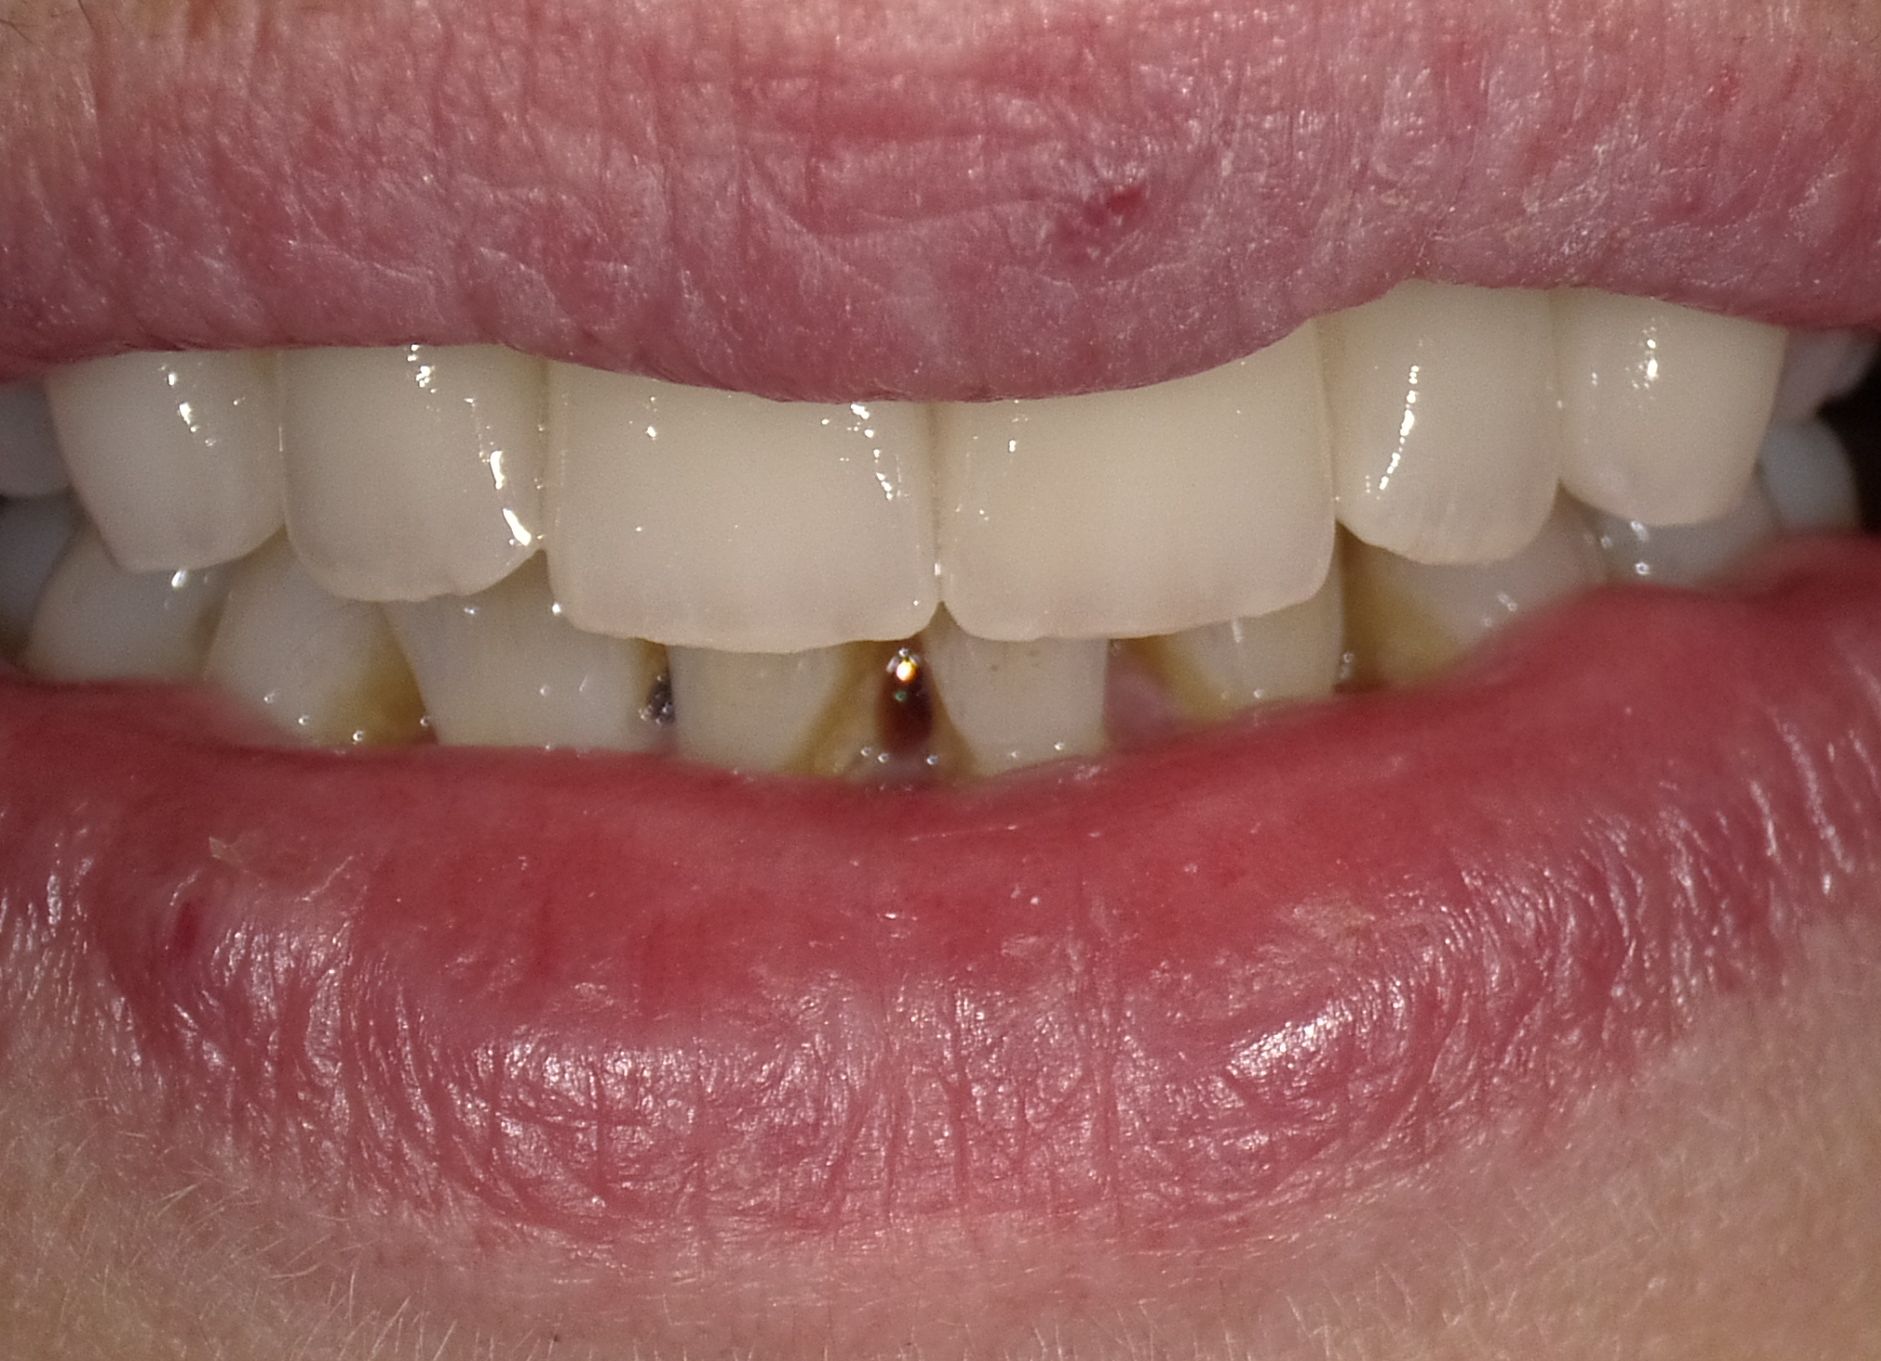

Diverse Vorbehandlungen mit für die Patientin absolut inakzeptablem Ergebnis

Vorher: Diverse Vorbehandlungen mit für die Patientin absolut inakzeptablem Ergebnis

Komplette Veränderung mit vollkeramischen Kronen und Veneers in nur 2 Langzeitterminen; auch hier nachher ganz anderes Auftreten der Patientin, die ihre Zähne jetzt gerne zeigt und wieder gerne lacht

Nachher: Komplette Veränderung mit vollkeramischen Kronen und Veneers in nur 2 Langzeitterminen; auch hier nachher ganz anderes Auftreten der Patientin, die ihre Zähne jetzt gerne zeigt und wieder gerne lacht